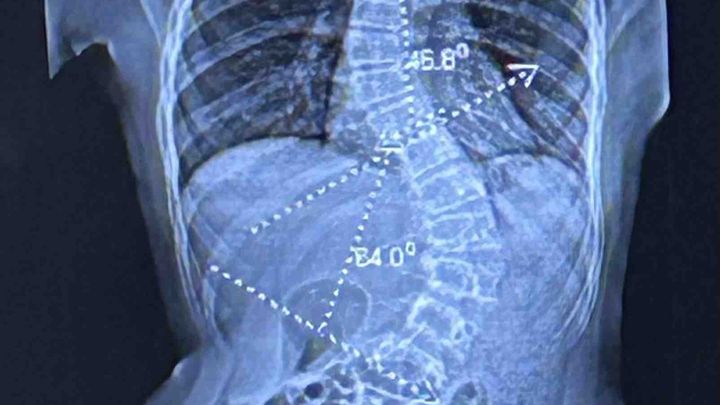

My name is Ava Wade. I just turned 14 years old and I suffer from scoliosis caused by chiari malformation. This means that my brain was too big for my skull, and it was going down into my neck, creating pressure on my spinal cord, resulting in my spine deformity. In July, I had to undergo Posterior Fossa Decompresson surgery. This is a brain surgery procedure where they removed a piece of my skull to make more space for my brain. Now, I have to get Spinal Fusion surgery to correct my scoliosis. My diseases have been extremely debilitating to my regular everyday life and have taken a huge toll to my mental health and overall life quality. These surgeries will help me return to my everyday life and improve my life quality, helping me to go back to the happy teenager I was before this. Any and all donations are greatly appreciated and all prayers too. Thank you.